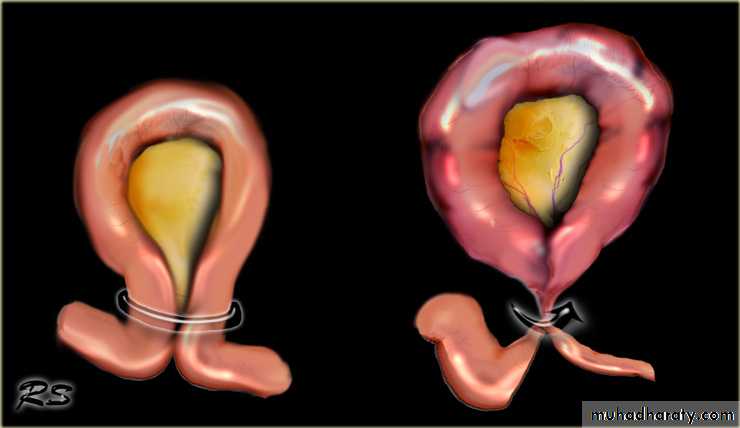

A volvulus is a twisting or axial rotation of a portion of bowel about its mesentery. The rotation causes obstruction to the lumen (>180° torsion) and if tight enough also causes vascular occlusion in the mesentery (>360° torsion).Bacterial fermentation adds to the distention and increasing intraluminal pressure impairs capillary perfusion. Mesenteric veins become obstructed as a result of the mechanical twisting and thrombosis results and contributes to the ischaemia.

This occurs secondary to intestinal malrotationand is potentially catastrophic.less than one year old with bilious vomitingurgent surgical exloration(ladd procedure)Acute intussusception

one portion of the gut invaginates into an immediately adjacent segment.Most in children, peak five and ten months.

is composed of three parts :• the entering or inner tube (intussusceptum);

• the returning or middle tube;• the sheath or outer tube (intussuscipiens).

The part that advances is the apex

the mass is the intussusception

the neck is the junction of the entering layer with the mass.

In most children, the intussusception is ileocolic.

In adults, colocolic intussusception is more common .